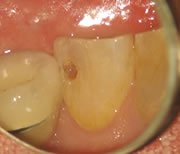

上のような小さな歯が、マイクロスコープではこのように見えています。

むし歯の治療(カリエス処置)

指の先ほどの歯の中の、むし歯の部分だけを除去しなければなりません。

むし歯の部分を取り損ねたら再発し、削り過ぎると歯を弱くしてしまうので、注意力と集中力が必要です。

マイクロスコープを用いれば視野を拡大して見られるため、健康な歯を痛めずむし歯の部分だけを除去できます。